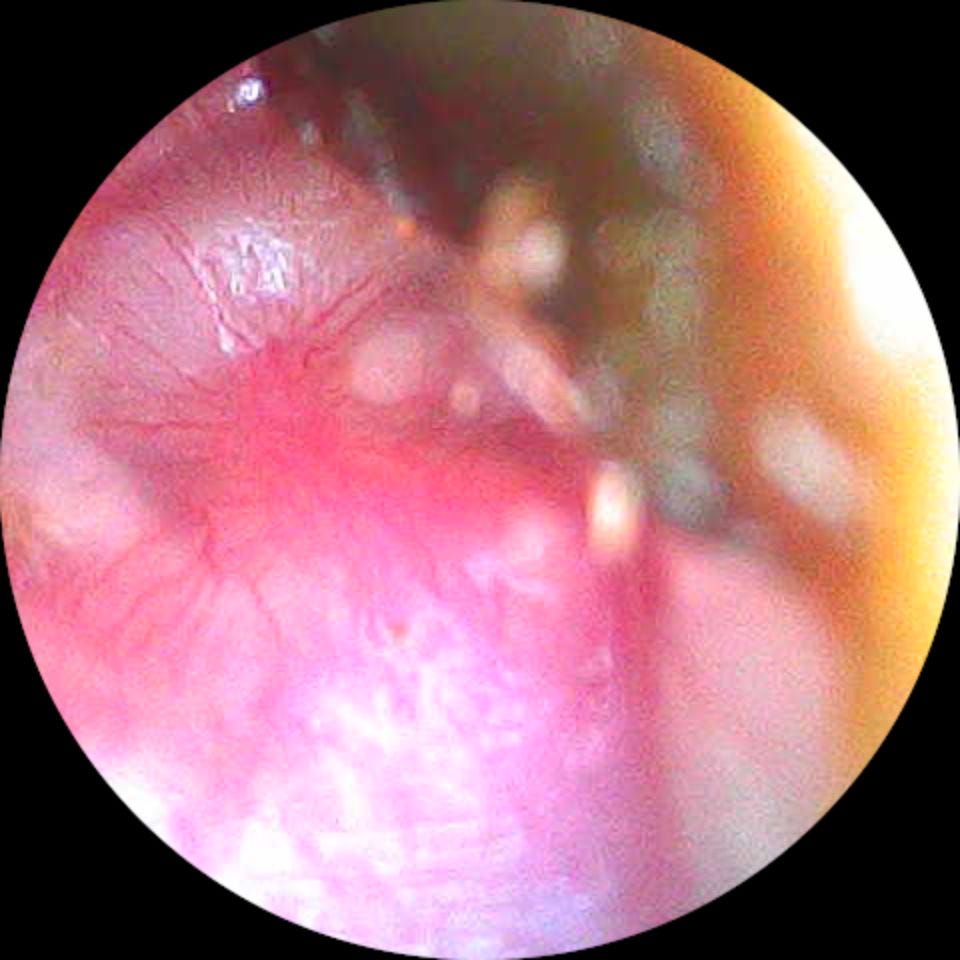

Oído Izquierdo

Es un fucking oído medio inflamado, no voy a permitir que me distraiga de la búsqueda de un horizonte que tanto me costó perseguir.